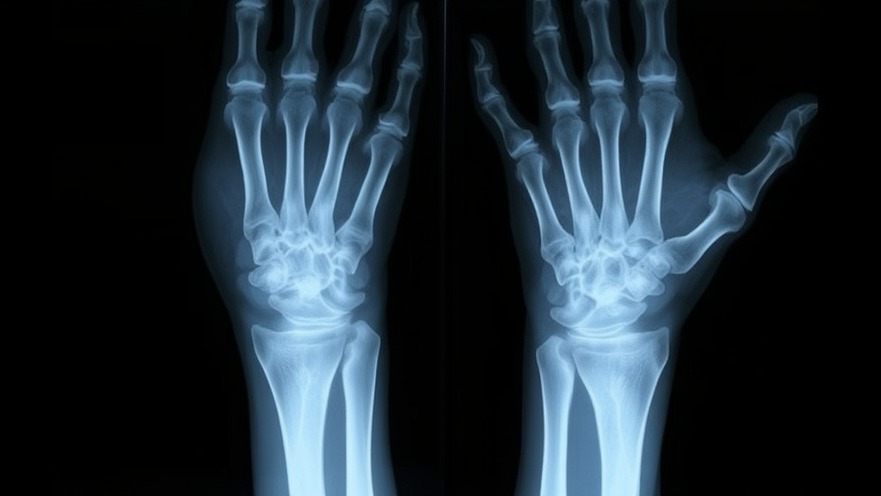

Detecting ulnar dysplasia early can make a significant difference in treatment. In some cases, prenatal ultrasounds can reveal anomalies before birth. However, it is most commonly diagnosed at birth. Following birth, healthcare providers typically use X-rays to assess bone structure and formulate a treatment plan. Genetic tests may also be recommended if the dysplasia occurs alongside other medical conditions.